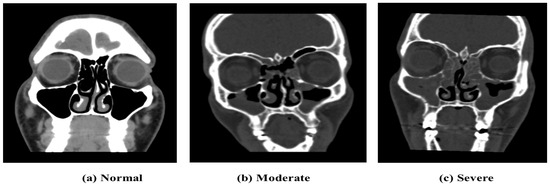

3.2. Data Labeling

The data labeling process involved consultation with professionals in the field, including two experienced radiologists specializing in sinus-related pathologies. Out of the total 2146 collected images, 1320 images were selected to be labeled by two experienced radiologists using the Lund-Mackay rating method to quantify the severity of the images. The labeled images, taken in the coronal view, were categorized into three classes: 0 (Moderate Sinus Cases), 1 (Severe Sinus Cases), and 2 (Normal Cases), as shown in Figure 3. After removing images of low image quality or those not belonging to the predefined categories, the final dataset comprised n = 1320 labeled images. The Lund-Mackay scoring system is considered to be one of the most commonly used approaches to classify the severity of ethmoid sinus pathologies in the case of sinusitis [41]. The Lund-Mackay scoring system evaluates various anatomical regions of the nasal cavity and paranasal sinuses based on the extent of opacification observed on CT scans or imaging studies. For instance, a score of 0 indicates no opacification in either maxillary sinus, while a score of 1 signifies partial opacification in one or both maxillary sinuses, and a score of 2 denotes complete opacification in one or both maxillary sinuses. Furthermore, the decision to focus on training only the Moderate and Severe classes was made to address the issue of imbalanced classes, prioritizing the severity levels that are of greater clinical relevance. The strengths of this system include the systematic and comprehensive analysis of several sinus regions, leading to an objective measure of disease severity. On the other hand, there is a limitation in its use, in its subjective interpretation, for the scoring depends on the individual differences in assessing the opacification.

Figure 3. CT scans’ illustration of severity levels.